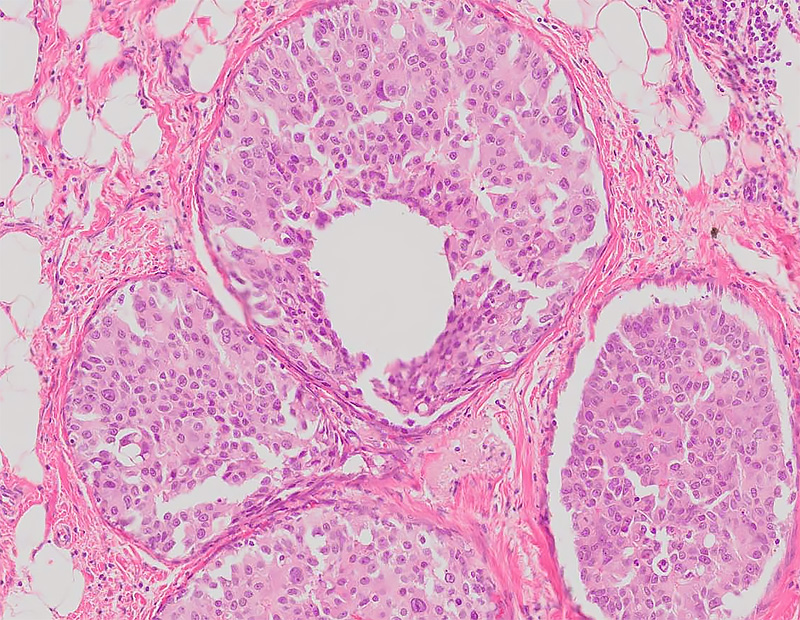

Histology is the microscopic study of living tissues. There are four basic types of tissue in the body: epithelial tissue, muscle tissue, connective tissue, and nervous tissue. Breast cancer is a malignant transformation of epithelial tissue (usually glandular tissue). Fat (adipose) and fibrous tissue are both connective tissues, which may also form into suspicious lesions that show up on a mammogram. The exact nature of the suspected tumor can almost always be confirmed on histological evaluation.

The histological grade of breast cancer is a measure of how much the cancer cells differ from normal breast cells. This grade helps predict the aggressiveness of the cancer and guides treatment options. Your Providence Saint John’s pathologist will determine the type of breast cancer and whether it is confined to the breast ducts (DCIS) or has reached infiltrative or invasive status. They will also assess if the cancer has metastasized to the lymph nodes in the axilla based on additional samples from that region.

The histological grade is determined by examining three key features of the cancer cells under a microscope:

- Tubule Formation: The degree to which the tumor cells form glandular structures.

- Nuclear Pleomorphism: The variability in the size and shape of the cell nuclei.

- Mitotic Count: The number of cells undergoing division.